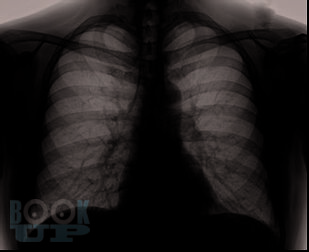

Хроническая обструктивная болезнь легких является одной из ведущих причин инвалидности и смертности населения.

В данном учебном пособии отображены основные критерии клиники и диагностики больных с патологией бронхолегочной системы. Подробно рассмотрены ведущие симптомы, которые встречаются у больного с ХОБЛ и требуют необходимости дифференциальной диагностики уже на амбулаторном приеме у врача-терапевта, отображены особенности течения заболевания, представлены алгоритм проведения дифференциальной диагностики заболевания и необходимый перечень обследования пациента в амбулаторных условиях. Разобрана тактика лечения больного с ХОБЛ в условиях первичного звена здравоохранения. Представлен раздел с тестовыми заданиями и клиническими задачами для самостоятельной работы.